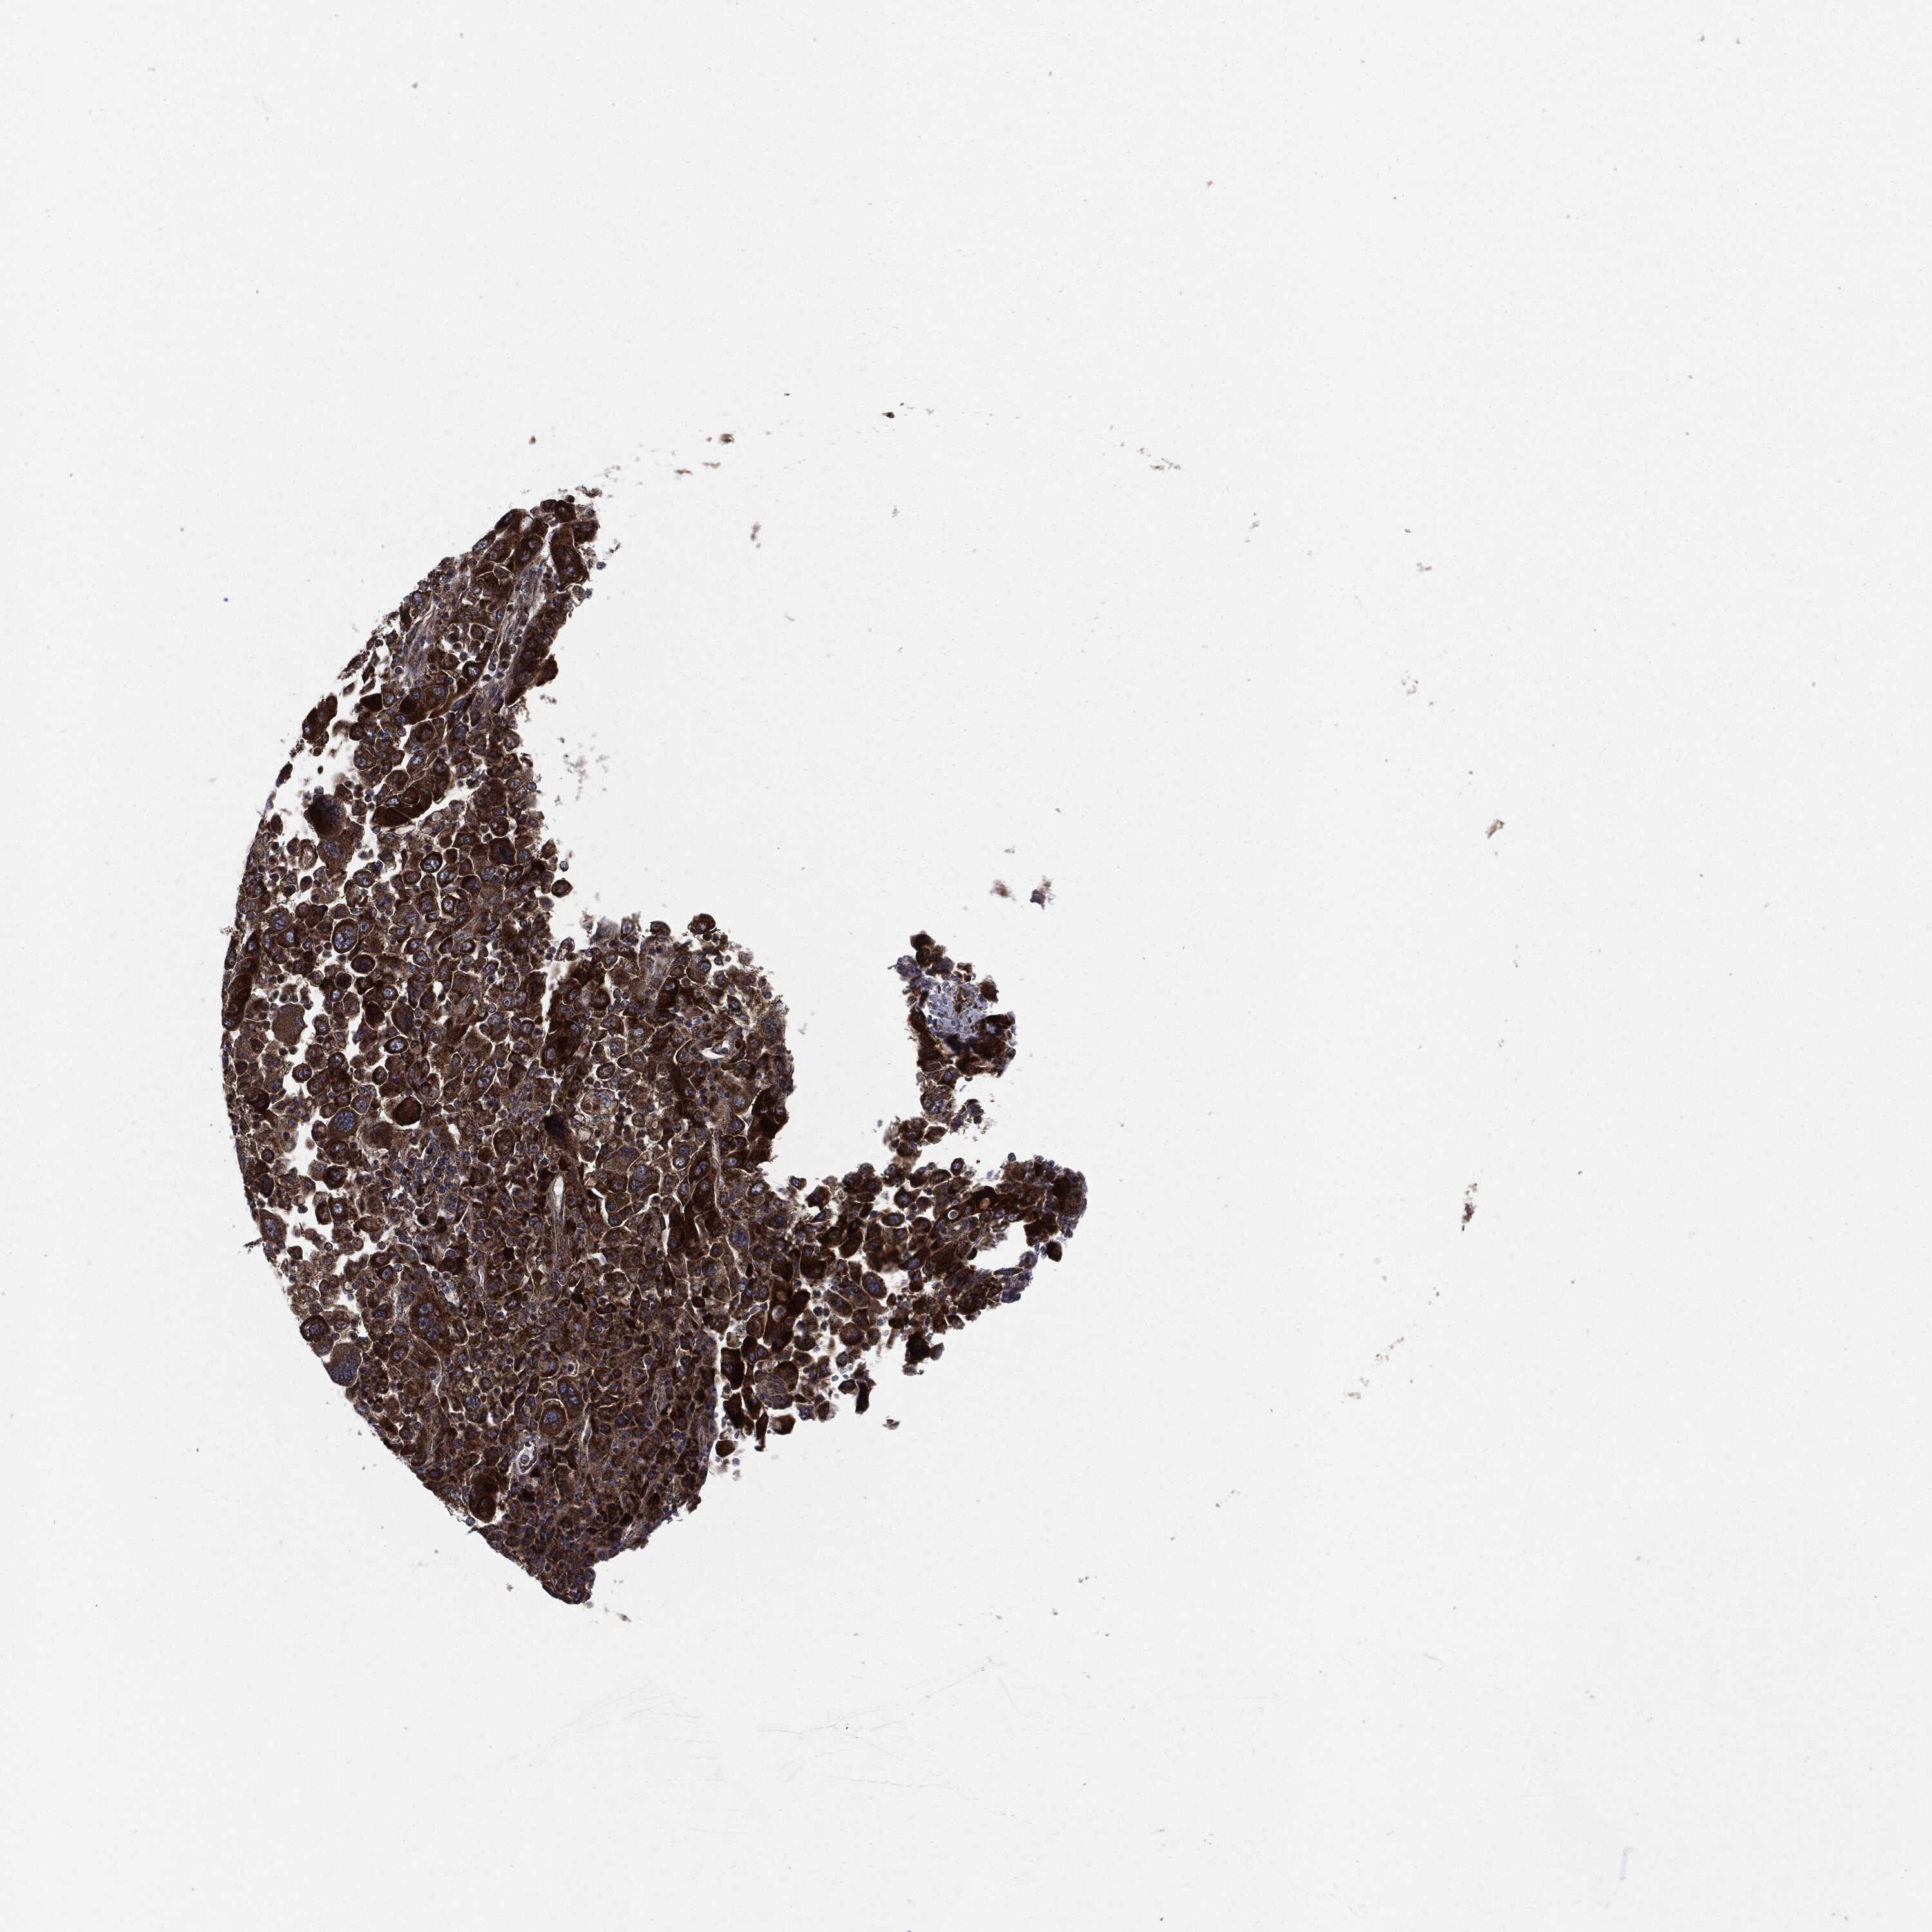

STOMACH CANCER - Protein expressioni

A mouse-over function shows sample information and annotation data. Click on an image to view it in a full screen mode. Samples can be filtered based on level of antibody staining by selecting one or several of the following categories: high, medium, low and not detected. The assay and annotation is described here.

Note that samples used for immunohistochemistry by the Human Protein Atlas do not correspond to samples in the TCGA dataset.

Antibody stainingi

Antibody staining in the annotated cell types in the current human tissue is reported as not detected, low, medium, or high, based on conventional immunohistochemistry profiling in selected tissues. This score is based on the combination of the staining intensity and fraction of stained cells.

Each image is clickable and will lead to virtual microscopy that enables deeper exploration of all samples and also displays staining intensity scores, fraction scores and subcellular localization as well as patient and tissue information for each sample.

Antibody HPA002640

Antibody CAB019291

Antibody CAB080384

Staining

High

Medium

Low

Not detected

Intensity

Strong

Moderate

Weak

Negative

Quantity

>75%

75%-25%

<25%

None

Location

Nuclear

Cytoplasmic/membranous

Cytoplasmic/membranous,nuclear

Adenocarcinoma, NOS

Adenocarcinoma, High grade